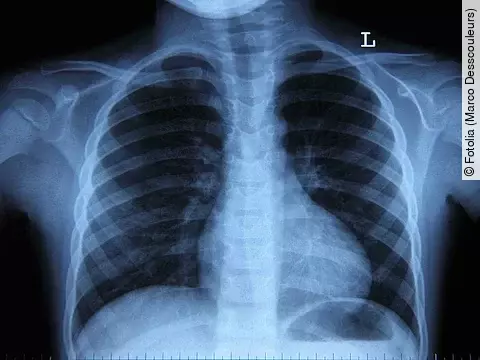

Mit jedem MRT- oder CT-Gerät können Radiologen auf diese Weise knapp 100 000 Euro Gewinn im Jahr machen. Nach Schätzung kostet dies die Versicherten jährlich knapp 200 Millionen Euro. Der finanzielle Anreiz führt offenbar auch dazu, dass Ärzte in Bundesländern mit den lukrativen Pauschalen bei ihren Patienten häufiger Untersuchungen mit Kontrastmitteln durchführen als in anderen Bundesländern - und somit häufiger, als es medizinisch nötig wäre. Die Mittel bergen aber, wie jedes Medikament, Gesundheitsrisiken.